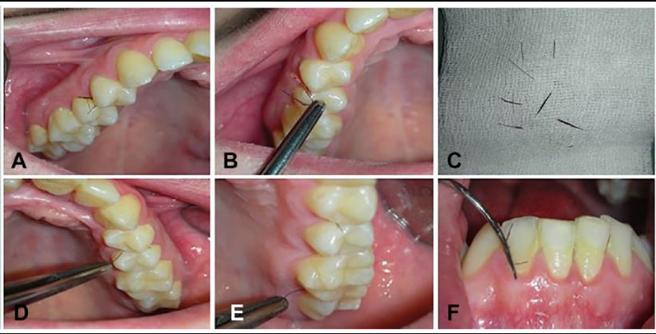

Una joven italiana sufre una extraña enfermedad que hace que le crezca vello entre los dientes.

Una mujer italiana de 29 años sufre una extraña enfermedad que hace que le crezca vello entre los dientes. “Este es un caso raro de hirsutismo”, explicó una especialista.

Entre los dientes de la paciente encontraron pequeños trozos de vello en forma de pestañas,por lo que doctores decidieron operarla y recetarle anticonceptivos orales con el fin de regular los cambios hormonales.

“Dado que el hallazgo se repitió seis años después de la primera observación, esto llevó a nuestra comprensión de que este no era un hallazgo ocasional, sino que probablemente era un defecto estructural y un desequilibrio hormonal que persistió, dando lugar a este fenómeno”, aseguró Khrystyna Zhurakivska, investigadora de la clínica dental de la Universidad de Foggia (Italia), y quien trató a la paciente.

En ese sentido, agregó: “La aparición de cabellos en la cavidad oral es un evento extremadamente raro y sus causas son desconocidas. Este es un caso raro de hirsutismo”.

Se denomina hirsutismo al desarrollo excesivo de vello, especialmente en las mujeres, provocado por un trastorno de las glándulas suprarrenales. Al producir más testosterona de lo normal, comienza a salir pelo en lugares fuera de lo común.